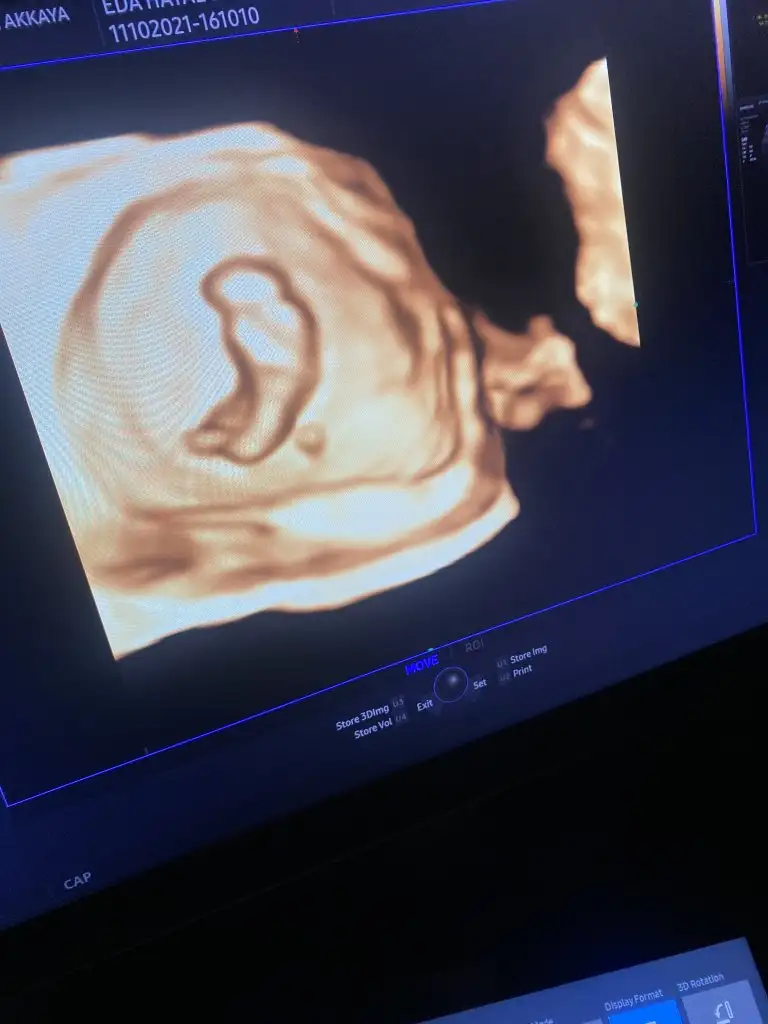

fotolarda görüldüğü üzere parmak emenler kulübünden, aç kaldı yavrucak

%90 erkek dedi